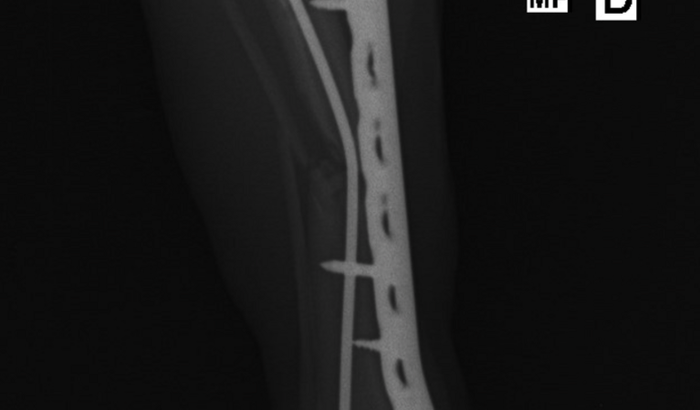

Meu cachorro eSta ainda com.os pontos ,manca pois ainda eSta quebrado e alem de tudo com.os.pinos e ferro fora eSta sofrendo com isso